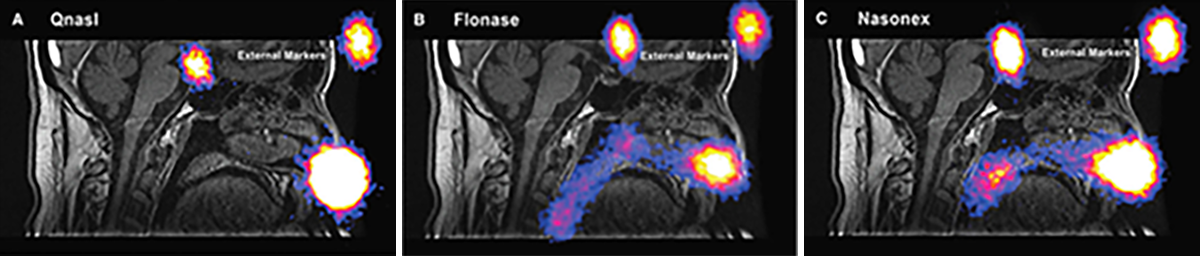

Both traditional spray pumps and pressurized metered-dose aerosols deliver a dose of medication primarily to the anterior segment of the nasal passage, which is lined with skin-like epithelial cells.[2] Much of the remaining medicine that does get past the nasal valve is drawn along the floor of the nose, under the inferior turbinate bone, by sniffing. Effective, targeted drug delivery for many therapeutic applications requires reaching the high and deep part of the nasal passages, which means drug must be delivered beyond the nasal valve and above the inferior turbinate bone to reach the broad surfaces lined by lung-like respiratory epithelium that surround sinus openings and where the nerves from the brain penetrate to carry sense of smell.

With currently available corticosteroids, given the amount of spray delivered close to the nasal opening, it is not surprising that a considerable portion of the total drug dose is deposited in this region, where it may drip and be wiped away or eventually be blown out of the nose.[2]

Depiction not for comparative purposes. Reprinted with permission from JOURNAL OF AEROSOL MEDICINE & PULMONARY DRUG DELIVERY 28/8, 2015, by Leach et al, published by Mary Ann Liebert, Inc., New Rochelle, NY.

The percentage of drug that is transported toward the back of the nasal passages has been shown to be mainly cleared along the floor of the nose, limiting its exposure to the entirety of the mucosal surface area where interchange with the cells and circulation takes place.